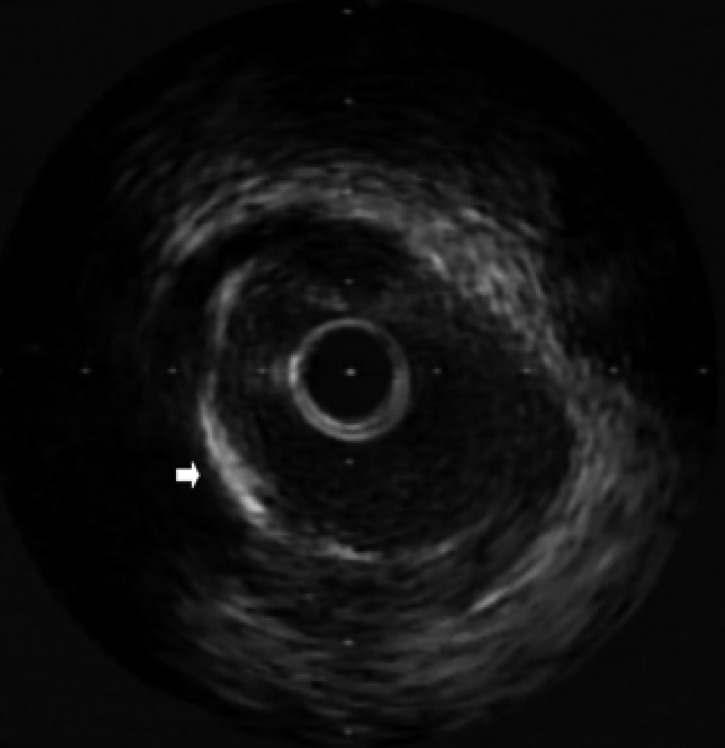

Figure 3

IVUS imaging at the left circumflex coronary artery site showed calcification (arrow).